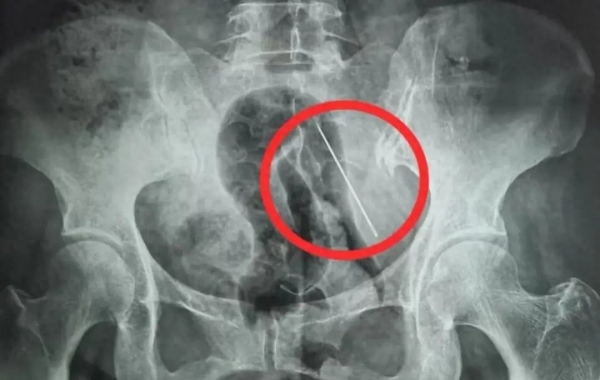

X光片显示张某腹部内有异物(医院供图)

据医院最新通报,老人因腰间别着缝衣针,抱娃时不慎受压,钢针直接刺入腹壁。医生紧急检查发现,钢针停留在皮下与肌肉层,万幸未穿透腹腔,没有伤到肠胃、肝脏等重要器官,否则后果不堪设想。

医护团队迅速开展微创手术,在影像定位下精准取出钢针,手术顺利完成。主治医生提醒:"体内异物千万不能自己拔,一旦移位刺破血管或脏器,会引发大出血、感染,危及生命。"